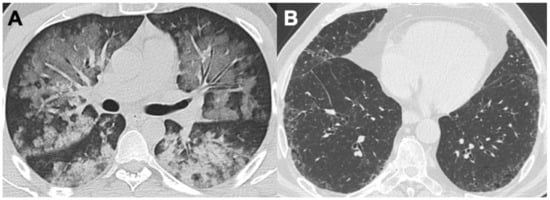

2.5. Eosinophilic Granulomatosis with Polyangiitis (EGPA)

| EGPA | Bronchial wall thickening; mucoid impaction, bronchiectasis | Tree-in-bud opacities; GGO; consolidations; diffuse alveolar hemorrhage (4%) | Pleural effusion | Dilatation of peripheral pulmonary arteries |